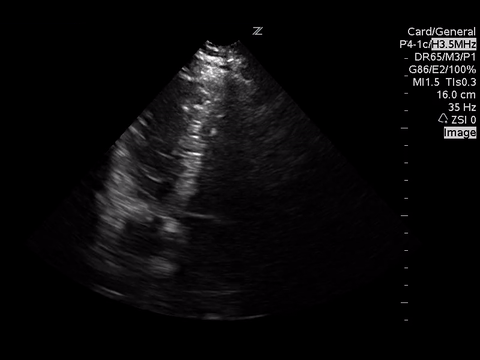

Below are three cardiac views. Think of what you would be looking for given the clinical scenario.

| PSLA |

Mostly with intermediate point of care echocardiography, in this patient, we would be looking for gross LV function using the “eyeball” method, presence of a pericardial effusion and rough RV:LV size.

In these images, we can estimate that the LV function is grossly normal and there is no pericardial effusion. Unfortunately, due to quality, we are unable to comment on the RV:LV size ratio. However, we would be looking for a RV:LV ratio of 0.6:1 as normal with a ratio of 1:1 as severe RV dilation.